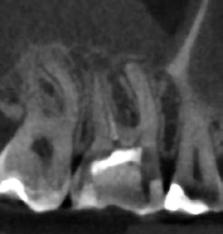

1. ábra: Kiindulási röntgenfelvétel. – 2. a–c. ábra: A horizontális irányú metszeten kiterjedt csontpusztulás jelei láthatóak (a), a vertikális irányú metszeteken mindkét középső metszőfognak megfelelően észlelhető a csontpusztulás (b–c).

3. ábra: Az eset ellátása során a „rezekciómentes” technikát alkalmaztuk. – 4. a–b ábra: Posztoperatív kontrollröntgen (a), 9 hónappal később készített kontrollfelvétel (b).

Egy fiatal hölgy, aki modellként dolgozik és emiatt nagy jelentőséget tulajdonít a saját fogai megőrzésének, a két középső alsó metszőfoga alatt kialakult duzzanat miatt kereste fel a rendelőnket. Vizsgálatot követően megállapítottuk, hogy a fogak mellett 20 mm szélességű tasak van jelen, amely az egyik alsó középső metszőfog disztális oldalától a másik alsó középső metszőfog disztális felszínéig terjed. Ebből az következik, hogy ezen a területen a teljes bukkális kortikális csontlemez leépült. Mindkét fog III. fokú mobilitással rendelkezett, amely tovább rontotta a kérdéses fogak várható prognózisát. Szenzibilitásvizsgálatot is végeztünk. A két alsó középső metszőfog esetében a páciens nem jelzett hidegingert, de a többi fog esetében fiziológiás választ adott. Periapikális röntgenfelvétel készült, amelyen nem mutatkozott meg a vélelmezett elváltozás (1. ábra). Ennek megfelelően CBCT-felvételt készítettünk, hogy jobban meg tudjuk vizsgálni a kérdéses területet. Ezen a felvételen már láthatóvá vált a vertikális és horizontális irányú csontpusztulás tényleges mértéke. A horizontális síkban készített metszeten a két alsó középső metszőfog körül megfigyelhető volt a bukkális kortikális csontlemez és a szivacsos csontállomány hiánya. A defektus szélessége 14,11 mm, a mélysége pedig 6,28 mm volt (2. a. ábra). A vertikális irányú metszeten láthatóvá vált, hogy a középső metszőfogak gyökerének bukkális oldalát nem fedi csont, és ez a defektus már a gyökércsúcsok alatti területre is kiterjedt (2. b–c. ábra)